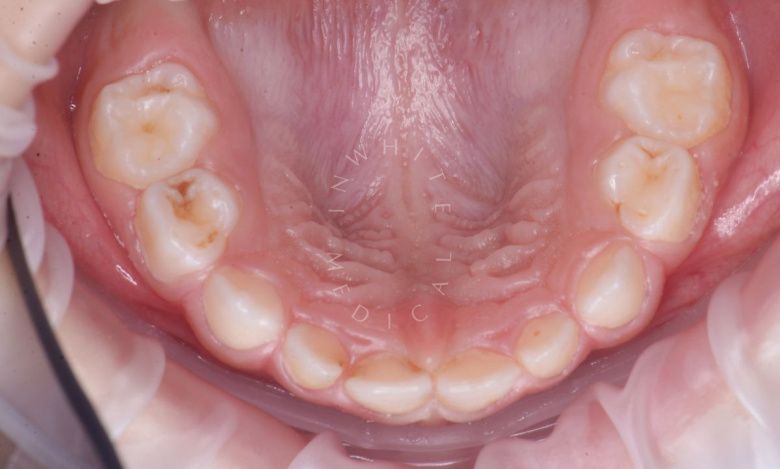

етская стоматология под наркозом Москва. Лечение молочных зубов и установка металлических коронок во сне - после процедуры